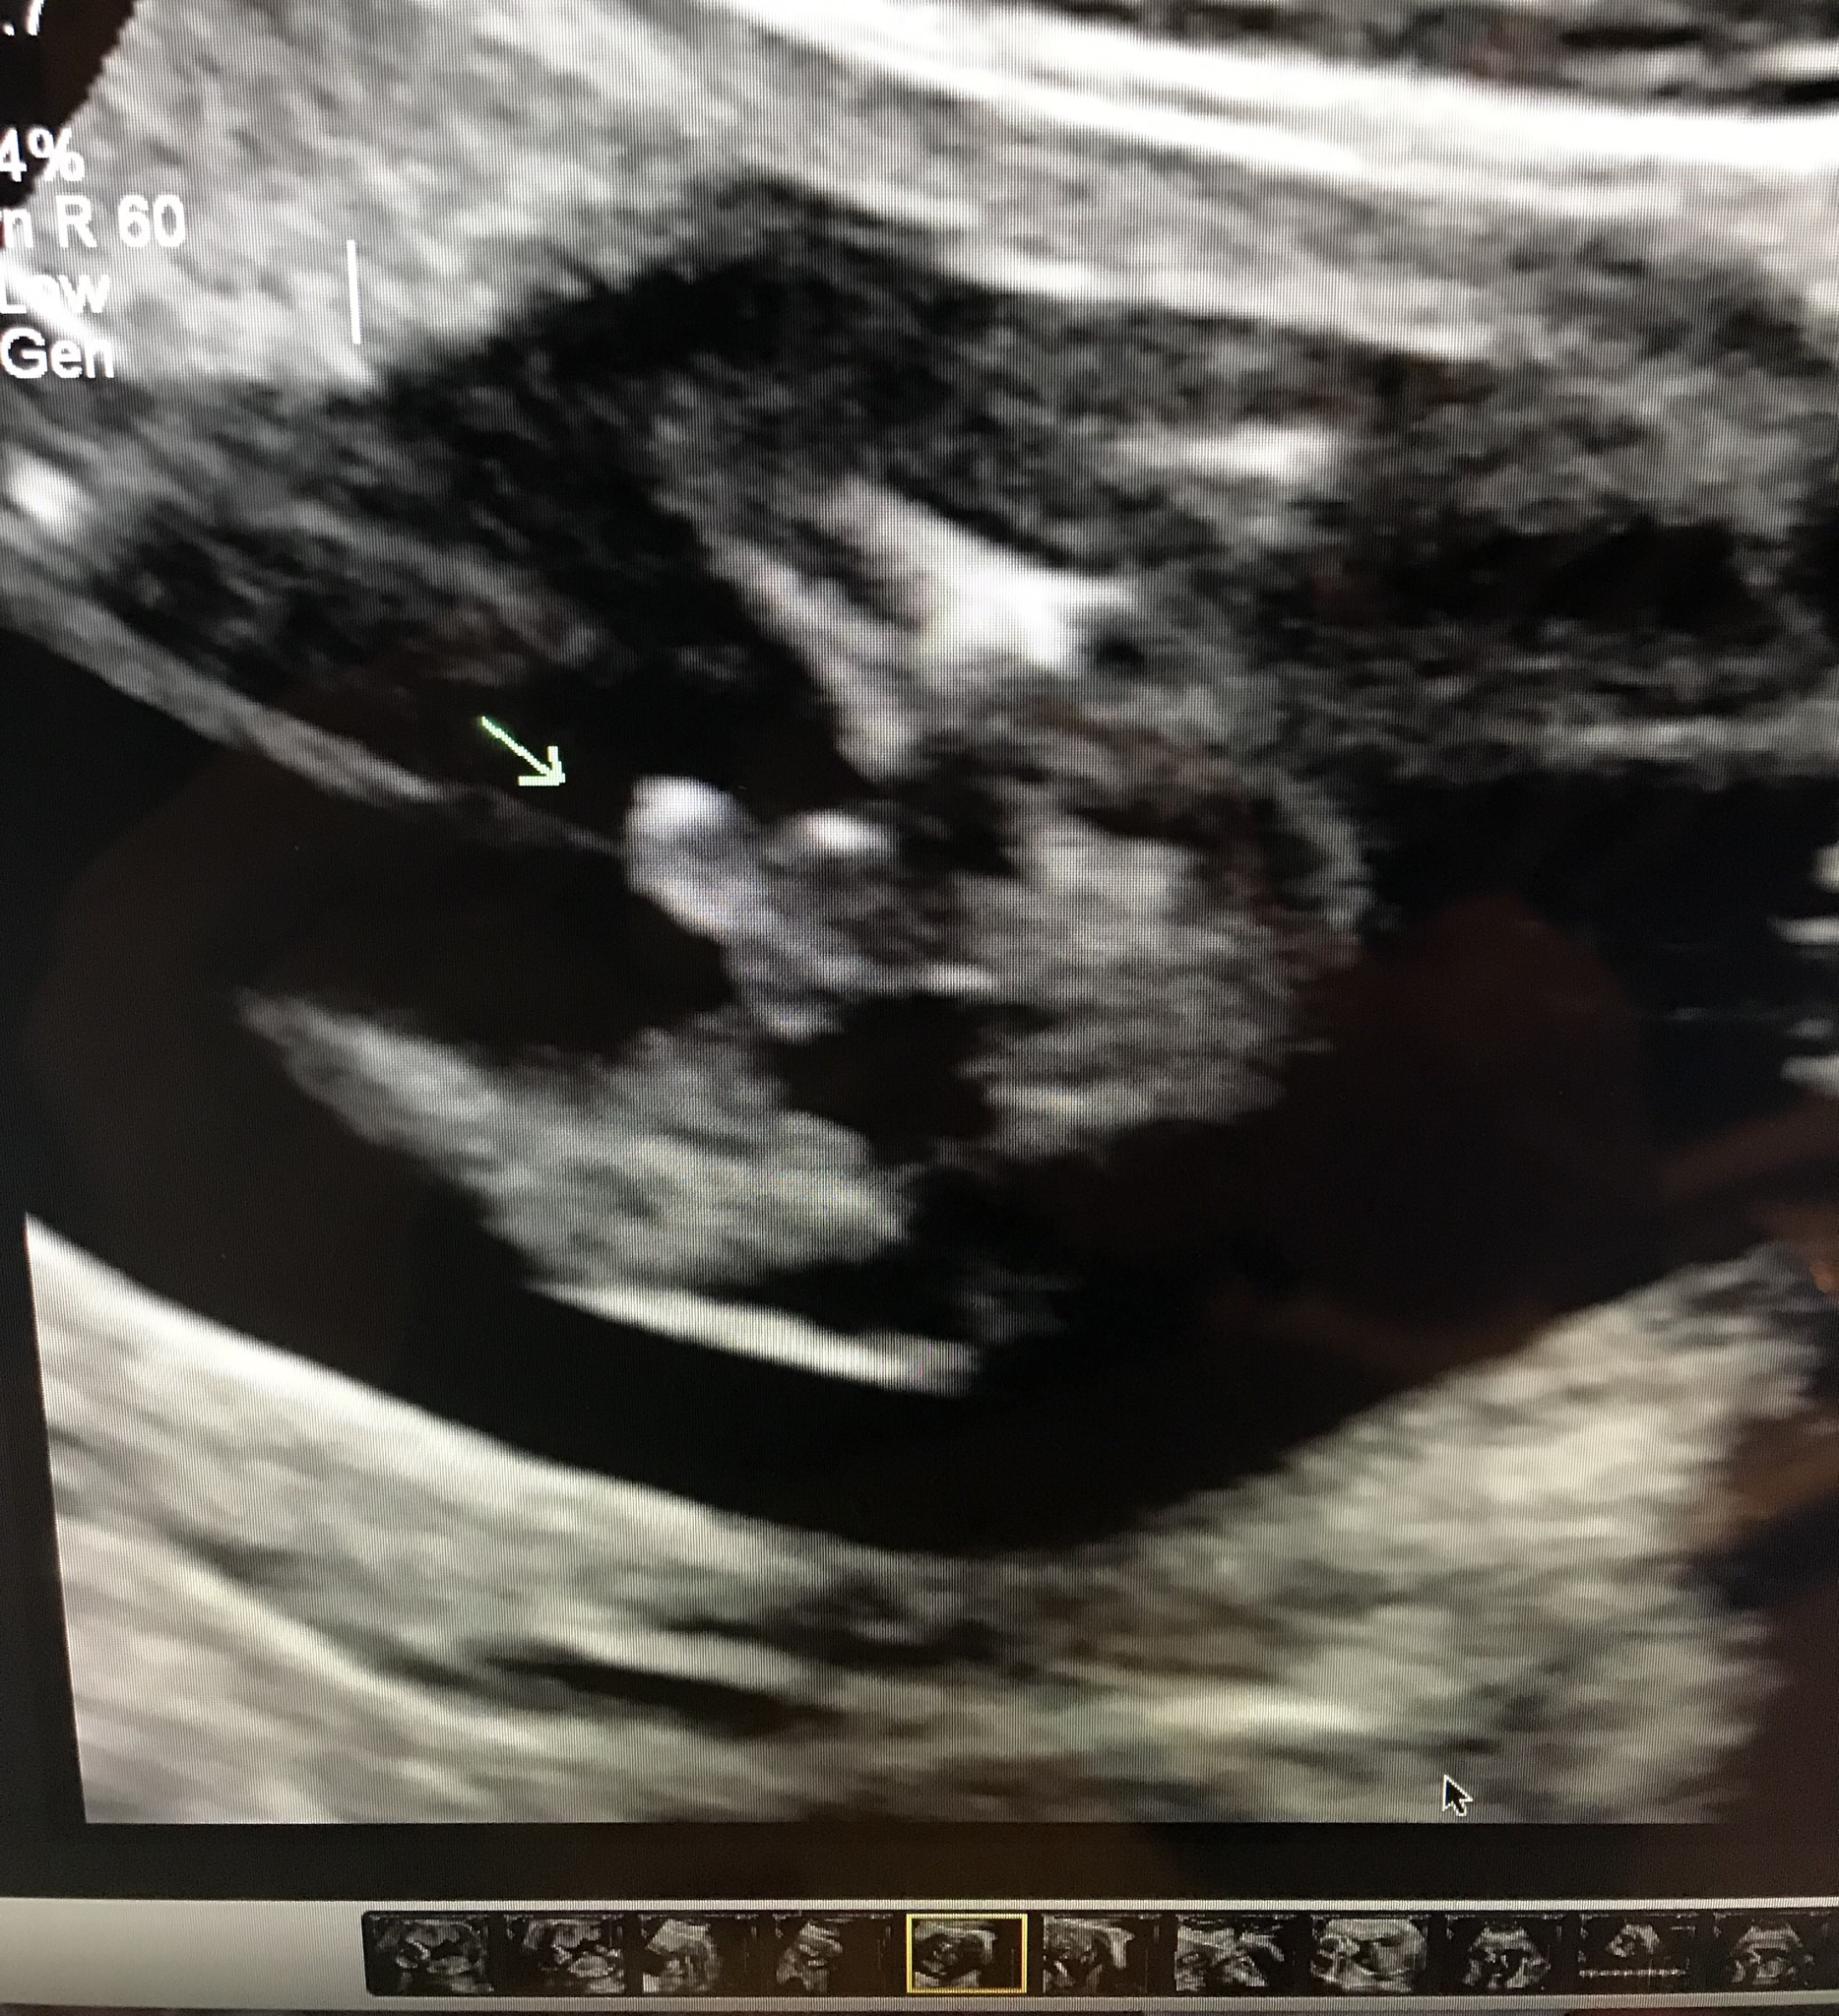

Is there any question?? Seems too out of proportion to be what we think it is!!

Thats definitely a boy! Congratulations!

But isn’t it too large? Seems like it could be umbilical

Boy

Definitely boy. That's a classic ultrasound shot for that gestation and my boys looked the same.

No thats a typical boy potty shot :-) trust me I've seen quite a few in my time having had 4 boys :bigsmile::bigsmile: